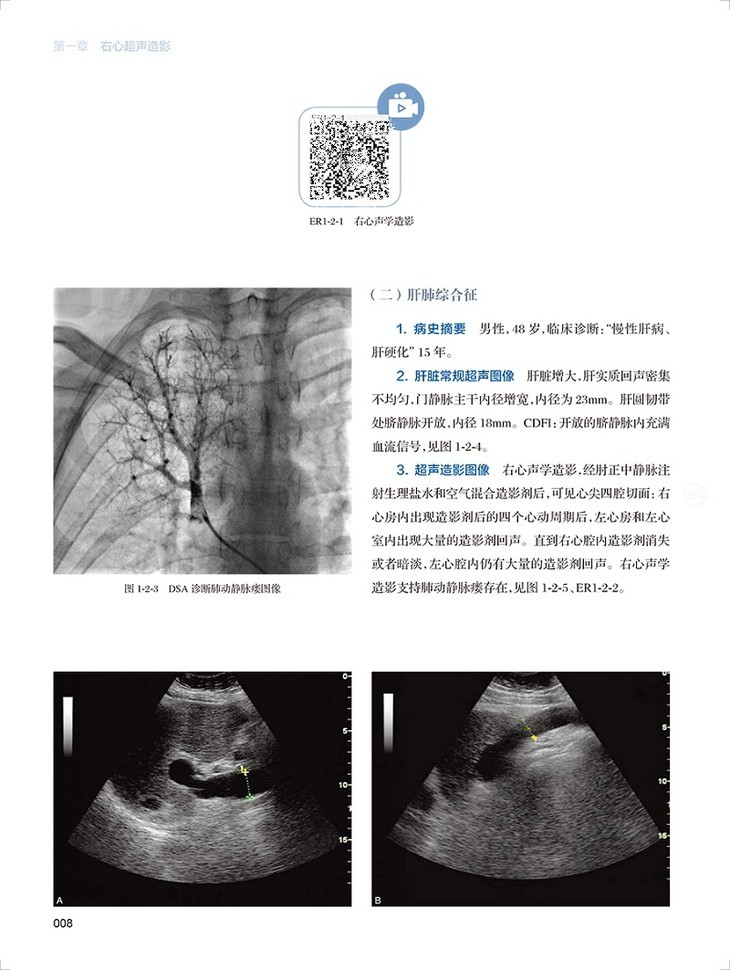

心血管超声造影图鉴共有文字内容60千字,图片454幅,视频212个。全书分为三章三十一节内容,分为左心超声造影、右心超声造影和血管造影三个板块,包括了卵圆孔未闭右向左分流、肺动静脉瘘、永存左上腔静脉、房间隔缺损封堵术后评估右向左的残余分流、部分型肺静脉异位引流、应激性心肌病、左心房黏液瘤、心腔内血栓等疾病的超声造影表现。每个病例分为病史概要、常规超声图像、超声造影图像、经食道超声心动图和超声造影要点五个小标题,内容精炼、脉络清晰、一目了然。各个病例配了多张彩图和视频进行对照,读者可以扫描图片右侧二维码观看视频,方便快捷。